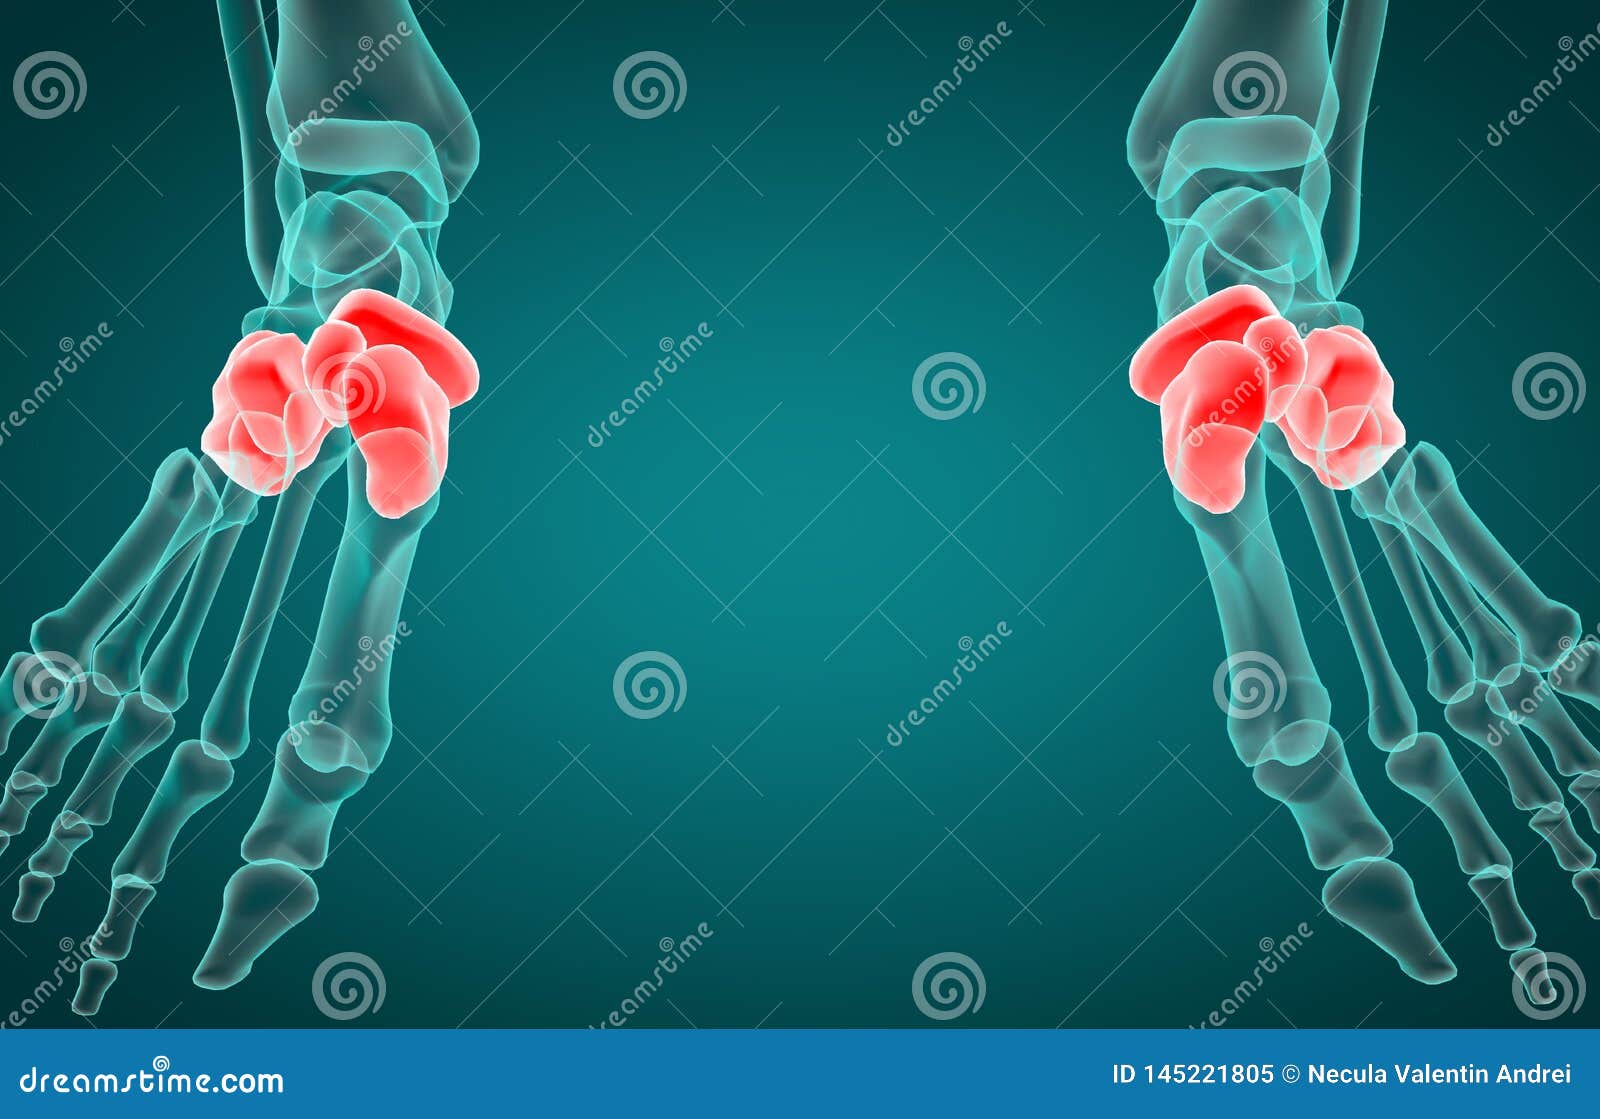

3D Illustration of Tarsal Bone, Xray Stock Illustration Illustration Tarsal Bones Labeled X Ray The tarsal bones of the foot are organised into three rows: Tarsal bones, collectively known as the tarsus, are a cluster of 7 irregularly shaped bones located in the lower ends of the tibia and fibula of each foot, composing the midfoot and hindfoot. Tali 4), historically known as the astragalus, is a tarsal bone in the hindfoot that articulates. Tarsal Bones Labeled X Ray.

From diagramweb.net